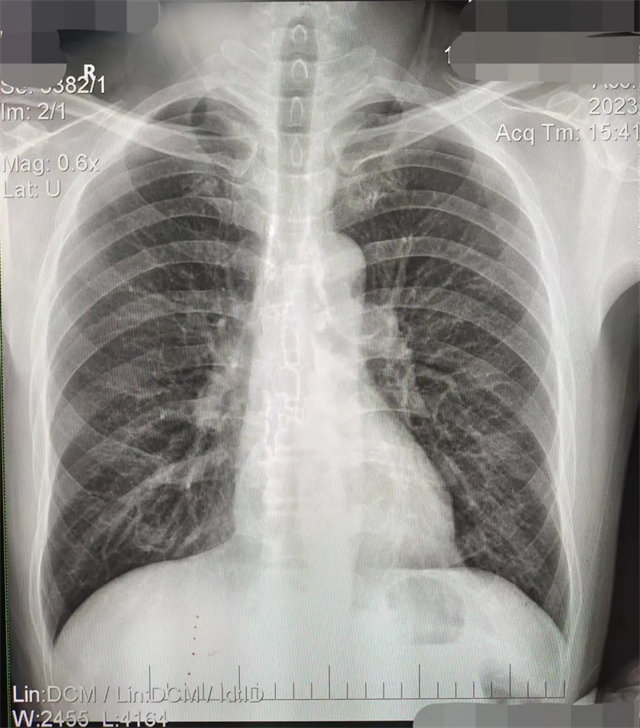

缺陷:双侧胸锁关节不对称,且有手机显影。

解决:去除手机后,使患者左侧紧贴成像件曝光。